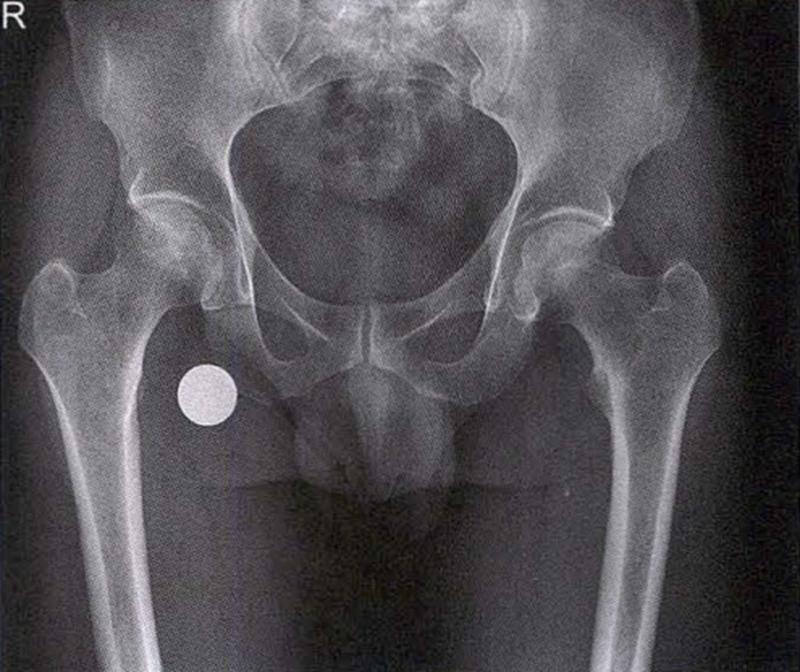

(1)X线检查

X线是诊断股骨头坏死的首选检查手段,常规拍摄髋关节正侧位片。早期股骨头坏死X线片可正常或显示股骨头外上方骨小梁稀疏;病情进展后逐渐出现密度增高、硬化带、囊性变等;晚期则出现股骨头塌陷、关节间隙变窄、Shenton's线不连续、骨关节炎改变等。硬化带和新月征是股骨头坏死X线特征性表现。在股骨头关节面塌陷变形早期上关节间隙不变或增宽后期随着骨关节炎加重关节间隙逐渐狭窄。

X线检查示右侧股骨头骨质密度不均匀